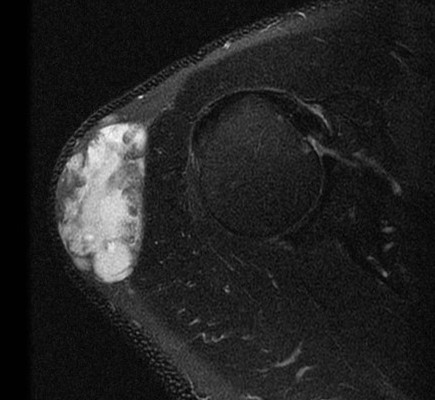

MRI

Deep to fascia / heterogenous

Liposarcoma vs Atypical Lipoma

Liposarcoma

- > 5 cm

- rapidly growing

- deep to fascia

- non homogenous on MRI